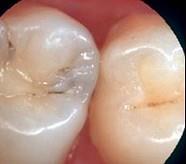

问题 龋好发于牙齿的 ( )

选项 A.滞留区 B.舌面 C.牙尖 D.自洁区 E.边缘嵴

答案 A